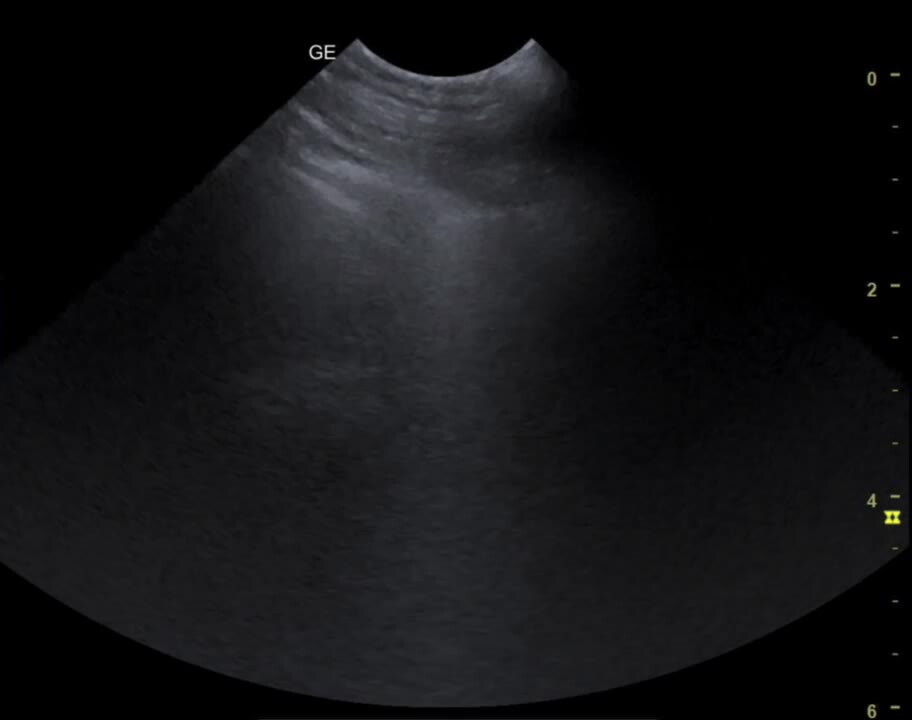

Abdominal, thoracic, and cardiac point-of-care ultrasound (APOCUS, TPOCUS, CPOCUS) techniques can be used to rapidly identify free abdominal, thoracic, or pericardial fluid; however, retroperitoneal and pelvic hemorrhage can be more challenging to identify:

• In the abdomen, the probe is focused on the ventral midline caudal to the xiphoid, over the urinary bladder, and on the right and left dependent flank regions.

• For the thorax, the probe is used to examine a minimum of four points of each hemithorax; however, any region may be examined.

• The cardiac window is used on the right and left sides (ribs 3-5, cranioventrally) to examine the heart.

A four-quadrant abdominocentesis can be performed if ultrasonography is not immediately available.